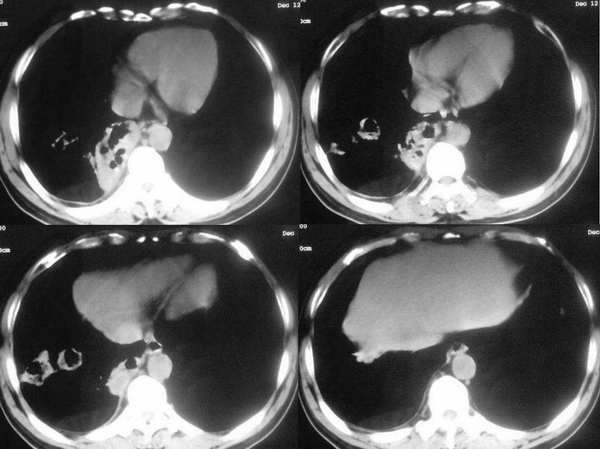

男,53,发热1月余,间断性,用药(不详)既停,停药既烧。有时吐痰、鼻涕带血。

右肺下叶基底段团状阴影,其内见多发不规则空洞,无液平;两肺多发大小不等结节影,纵隔淋巴结肿大,考虑:肺癌伴肺内及纵隔淋巴结转移

右肺下叶基底段及两肺多发大小不等结节影,其内见多发不规则空洞,无液平;纵隔淋巴结稍肿大,考虑:霉菌感染

右肺下叶基底段团块状病灶,其内见偏心性空洞,洞内未见液平面,可见壁结节;双肺野及双侧胸膜见多发大小不等软组织密度结节影,边缘较光滑,部分肺内结节有空洞形成;纵隔内见有重大淋巴结;右侧见少量胸腔积液。

结合临床考虑:1、右肺癌并双肺、胸膜转移,考虑鳞癌可能性大。2、纵隔淋巴转移。3、建议查痰找癌细胞。

影像表现:两肺大小不等结节,有融合、有空洞,洞壁薄厚不均,

双肺胸膜下见大小不等圆形类圆形结节影,边缘较光滑;右肺下叶基底段靠隔顶及纵隔旁见团块状病灶,其内见偏心性厚壁空洞,洞内见短液平面,壁厚薄不均。纵隔淋巴结增大;右侧见少量胸腔积液。

考虑:⑴双肺转移瘤可能大。⑵右下肺鳞癌伴双肺转移。⑶右下肺脓肿伴双肺血行播散。建议结合临床近一步检查。

两肺外周胸膜下可见多发大小不等的结节影,边缘稍模糊,可见细长毛刺,右肺下叶病灶部分融合成片状,内出现多房空洞,部分内有小液平面,内壁较光整,壁厚不规则。考虑真菌感染(隐球菌)。

ct所见;两肺胸膜下多发散在大小不一结节状影,部位以右侧为主,多在胸膜下,多数结节内可见不规则空洞,壁厚薄不均,未见液平。

影像表现:双肺大小不等的结节影 ,部分有融合,有空洞,洞壁厚薄不一,

临床表现:发热月余,间断性,用药即停,有时吐痰,鼻涕带血

两肺外周胸膜下可见多发大小不等的结节影,边缘稍模糊,可见细长毛刺,右肺下叶病灶部分融合成片团状,内出现多房空洞,部分内有小液平面,内壁较光整,壁厚不规则。气管前腔静脉后淋巴结肿大。考虑1韦格氏肉芽肿。2真菌感染(隐球菌)。其他待排。

两肺大小不等结节及空洞多位于肺的外周部,空洞壁厚薄不均,结合临床表现,支持肺韦格肉芽肿诊断。